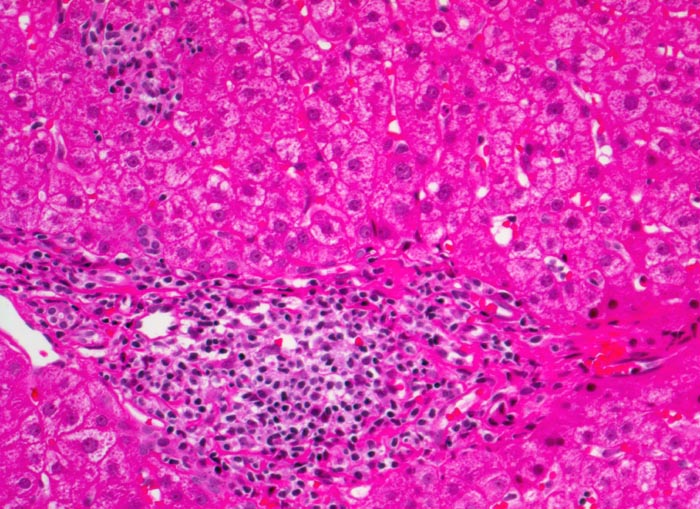

chronische Hepatitis C mit geringgradiger Aktivität

Portalfeld mit starker Vermehrung mononukleärer Entzündungszellen. Daneben ein intralobuläres Entzündungsinfiltrat mit gleicher Zusammensetzung wie das portale Infiltrat.

Fibrose der Portalfelder mit portoportaler Septenbildung.

Intravenöser Drogenabusus vor 10 Jahren. Damals Infektion mit dem Hepatitis C Virus.

Für die Ermittlung des Schweregrades der Entzündungsaktivität bei chronischer viraler Hepatitis wird die portale, die periportale und die intralobuläre Entzündung beurteilt sowie das Vorliegen von Apoptosen und Parenchymnekrosen. Es existieren verschiedene unterschiedlich komplexe Gradierungsschemata, welche je nach Präferenz der zuweisenden Gastroenterologen zur Anwendung kommen.

200